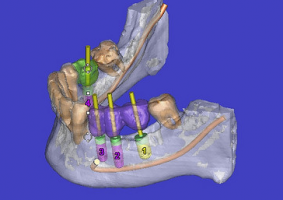

Die digitale Volumentomographie (engl. Cone-Beam CT - CBCT) ist ein modernes, dreidi-mensionales Röntgenverfahren für den Zahn-, Mund- und Kieferbereich. Mit den herkömmlichen Röntgenverfahren konnte der behandelnde Zahnarzt den Kiefer und die Zähne lediglich zweidimensional betrachten, doch nun liefert die „dritte Dimension“ die Möglichkeit für eine detaillierte räumliche Ansicht.

Mit dem DVT lassen sich anatomische Strukturen bei der Planung vor operativen Eingriffen, wie z. B. in der Implantologie, aber auch im Vorfeld von endodontischen Behandlungen exakter und detailgetreuer als auf herkömmlichen Röntgenbildern darstellen was mögliche Risiken minimieren und Misserfolge vermeiden kann.